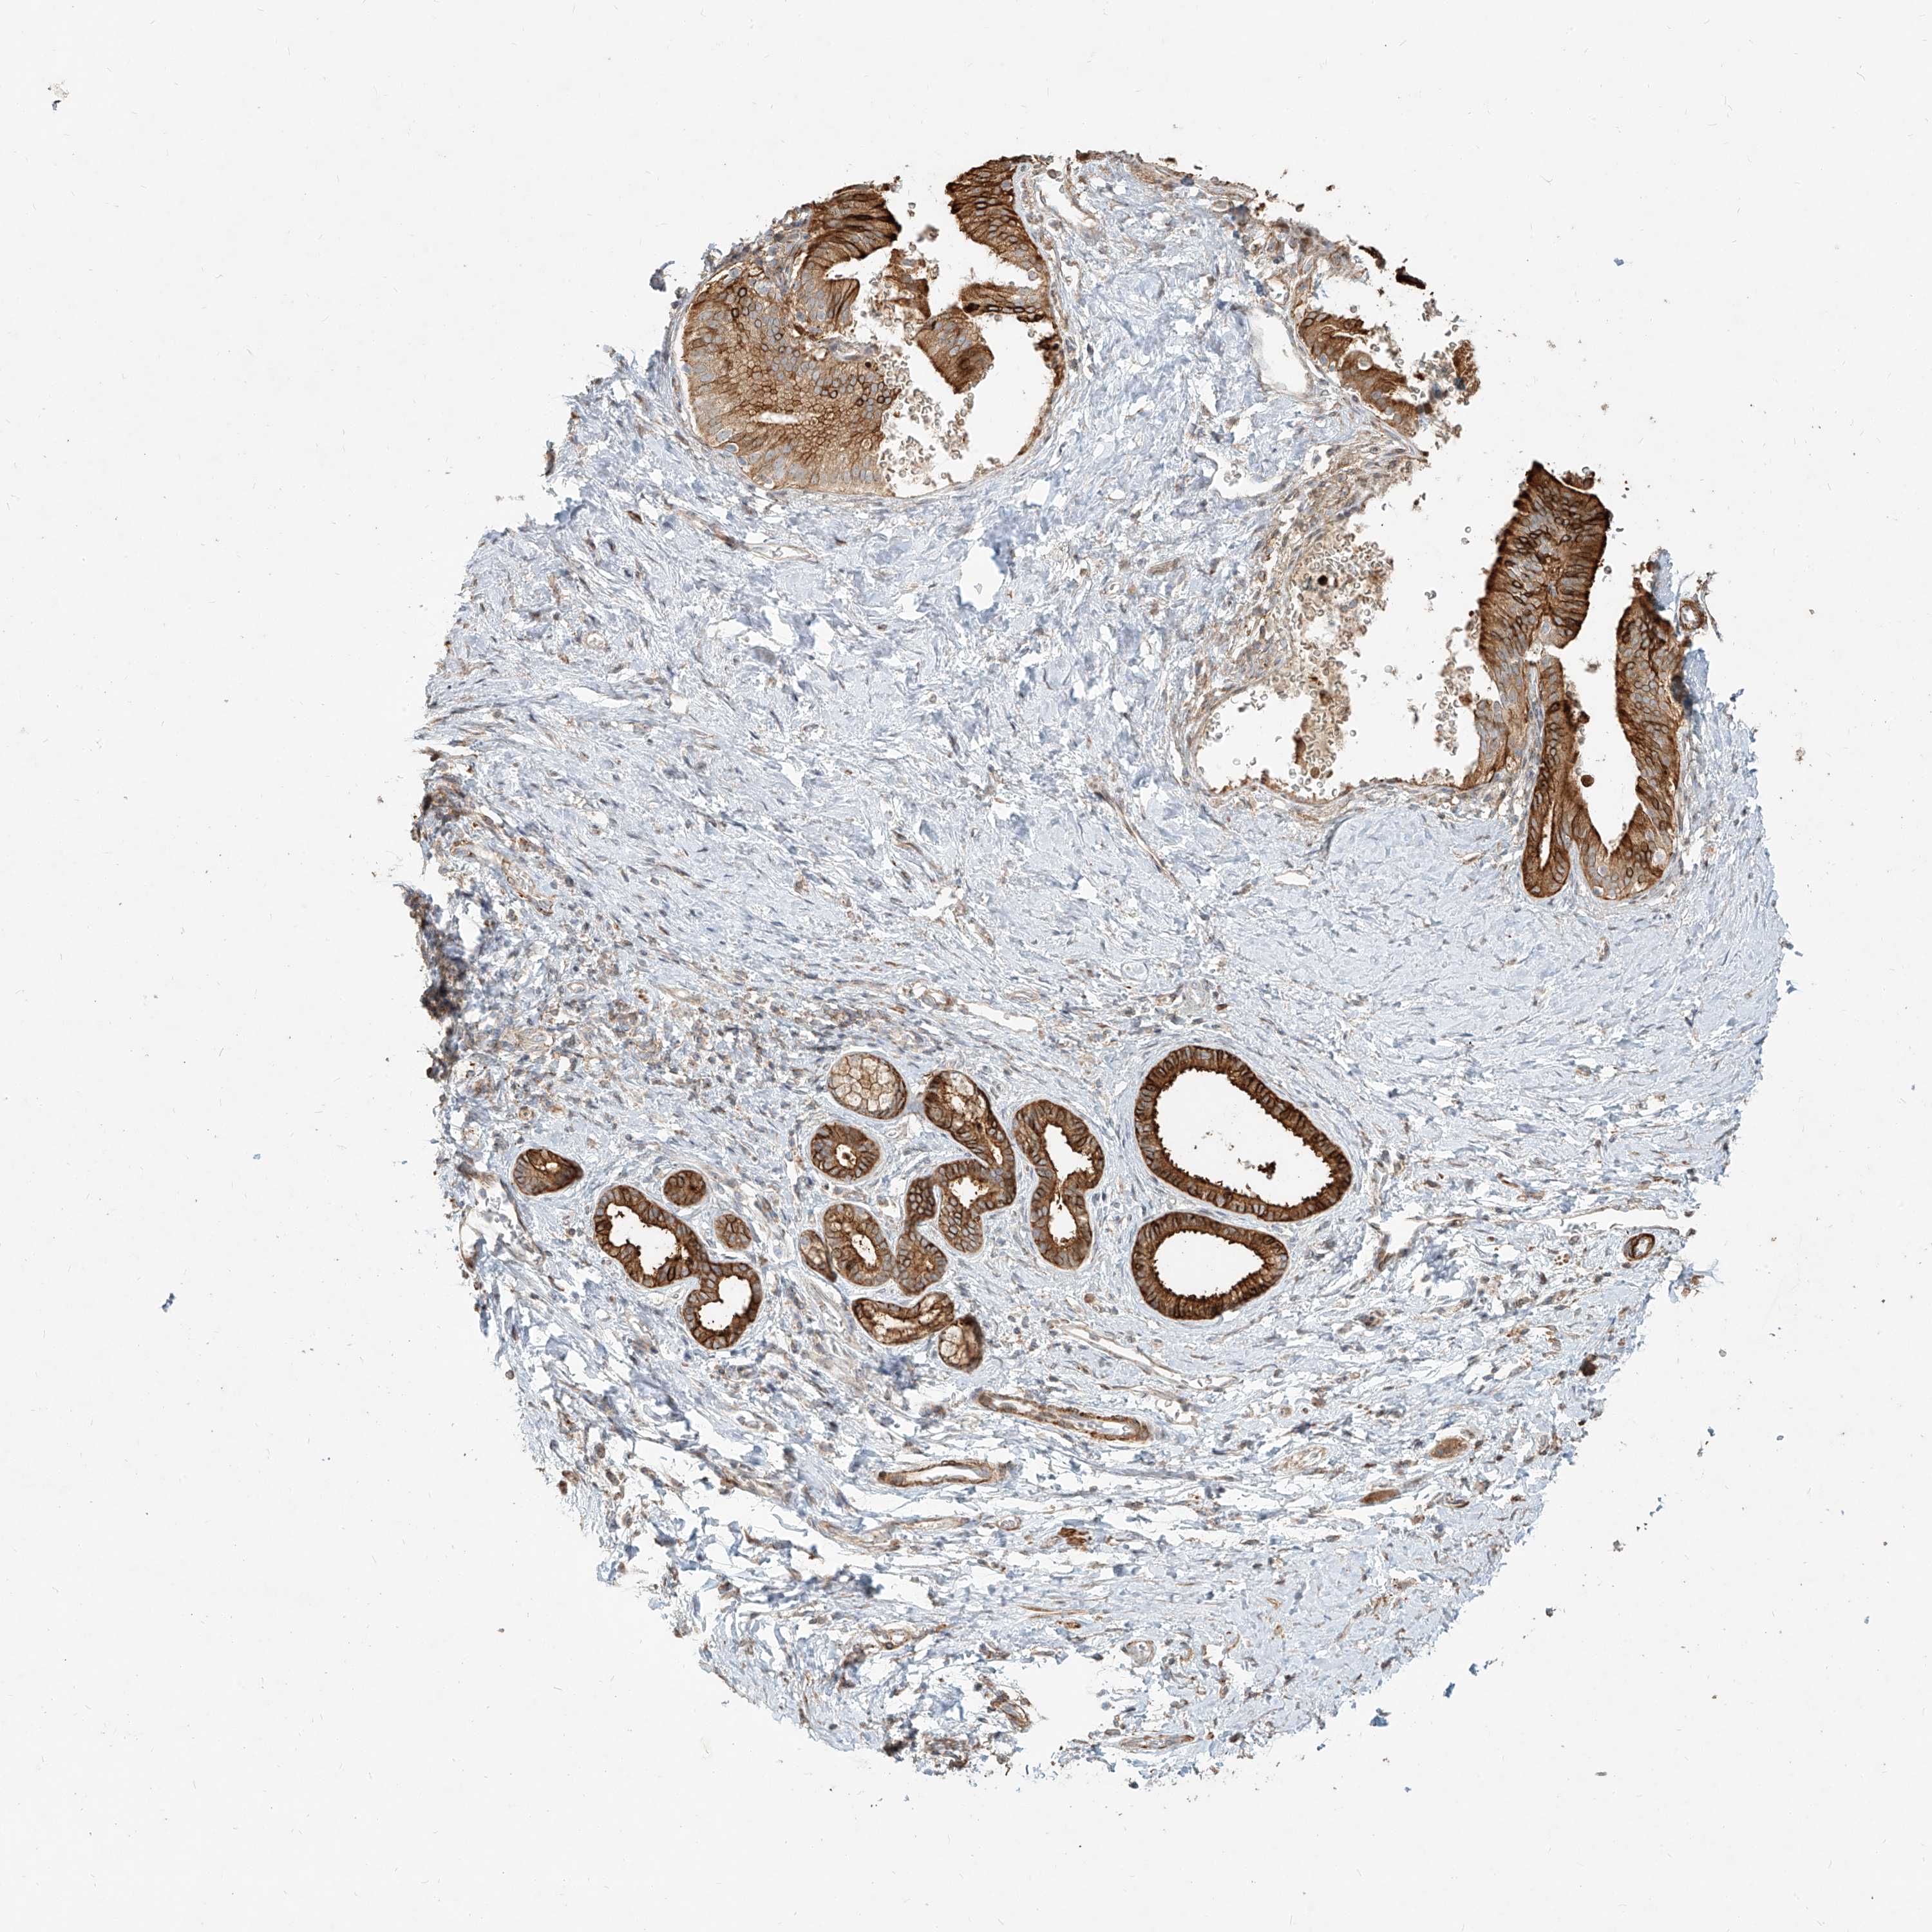

PANCREATIC CANCER - Protein expressioni

A mouse-over function shows sample information and annotation data. Click on an image to view it in a full screen mode. Samples can be filtered based on level of antibody staining by selecting one or several of the following categories: high, medium, low and not detected. The assay and annotation is described here.

Note that samples used for immunohistochemistry by the Human Protein Atlas do not correspond to samples in the TCGA dataset.

Antibody stainingi

Antibody staining in the annotated cell types in the current human tissue is reported as not detected, low, medium, or high, based on conventional immunohistochemistry profiling in selected tissues. This score is based on the combination of the staining intensity and fraction of stained cells.

Each image is clickable and will lead to virtual microscopy that enables deeper exploration of all samples and also displays staining intensity scores, fraction scores and subcellular localization as well as patient and tissue information for each sample.

Antibody HPA031550

Antibody HPA031551

Antibody HPA031552

Staining

High

Medium

Low

Not detected

Intensity

Strong

Moderate

Weak

Negative

Quantity

>75%

75%-25%

<25%

None

Location

Nuclear

Cytoplasmic/membranous

Cytoplasmic/membranous,nuclear

Adenocarcinoma, NOS